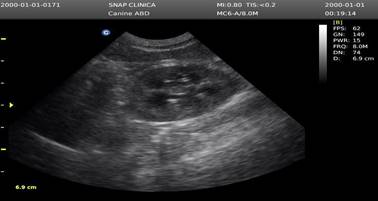

En la Figura 4 la evaluación ecográfica reveló una corteza renal hiperecogénica, sugiriendo un cuadro de LRA secundaria a la ingesta de AINEs. Ante este hallazgo, se procedió con el protocolo de emergencia, cuya primera medida fue la interrupción de la administración del fármaco. Posteriormente, la confirmación diagnóstica se obtuvo mediante analítica sanguínea (hemograma y bioquímica), lo que permitió personalizar la terapia de soporte y el manejo sintomático necesarios para la estabilización del paciente.